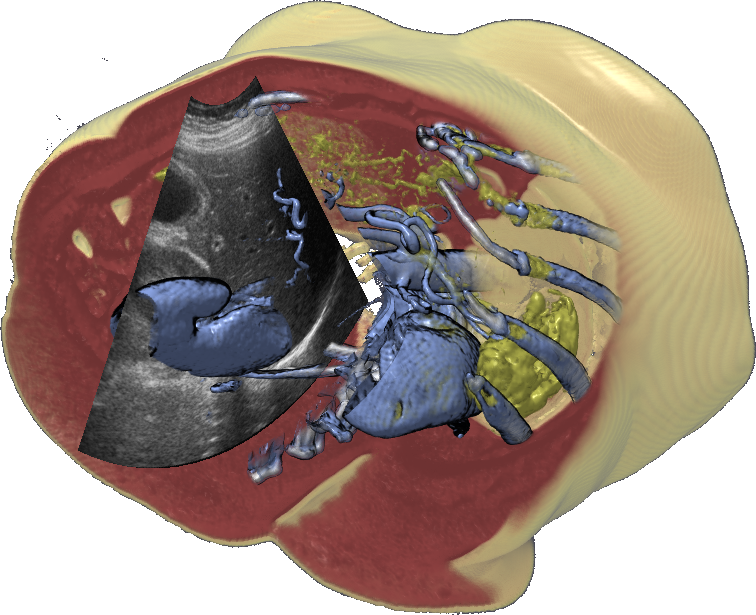

In addition, co-registration techniques enable use of multi-modal data sets. Fusion imaging, where ultrasound is combined with either CT, MRI, or PET images, allows for more precise navigation in ultrasound-guided interventions. This challenging new arena demands advanced visualization research to enlighten how different data types can be combined and presented in novel ways.

Burns et al. applied illustrative cut-aways combined with 3D freehand ultrasound burns07 . This provide a better spatial overview for the ultrasound images. To add more information onto the 2D ultrasound image, Viola et al. proposed an approach to enhance the ultrasound image by overlaying higher order semanticsviola08 , in this case in the form of Couinaud segmentation. The segmentation is pre-defined in a CT dataset and visually verified using exploded views. To combine it with ultrasound images, CT dataset is co-registered with the ultrasound using rigid transformation according to user defined landmarks. The different segments are superimposed onto the ultrasound image enabling the user to directly see which segments are in the visible. To improve ultrasound video analysis, Angelelli et al. used a degree-of-interest (DOI) function superimposed on the image angelelli10 . The video sequence was presented as a graph, where the height was defined by the amount the current ultrasound image covered the DOI-function.

Nikas et al. published an evaluation of the application of co-registered 2D ultrasound and MRI for intra-operative navigation nikas03 . Ultrasound based navigation shows promising results due to live acquisition at high frame rates and easy portability. For prostate brachytherapy a combination of ultrasound and co-registered CT can be used, as shown by Fuller et al. fuller05 . Existing commercial products apply optical tracking for intra-operative navigation during neurosurgery sonowand11 . Figure 5 shows how ultrasound and MRI can be blended together into a single reference frame burns07 .